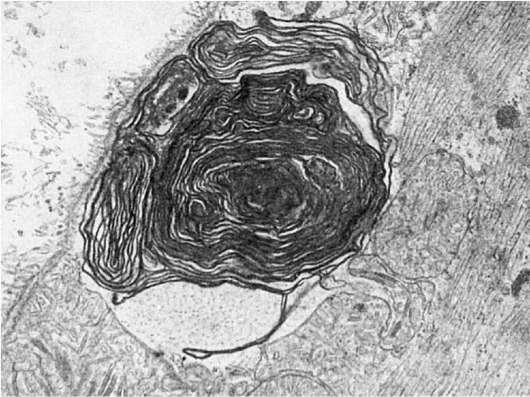

Своеобразным изменением плазмолеммы, встречающимся не только при нарушении ее проницаемости, является образование миелиноподобных структур (рис. 24). Эти структуры появляются в связи с перекисным окислением липидов мембран, усиливающимся под воздействием разных агентов. Высвобождающиеся из разрушающихся при перекисном окислении мембран фосфолипиды (дезагрегация и реагрегация мембраны) образуют сложные миелиноподобные структуры. Подобные структуры появляются и при скручивании удлиненных цитоплазматических отростков.

Рис.

24. Миелиноподобные структуры под плазматической мембраной мышечного волокна при ишемии. х22 500